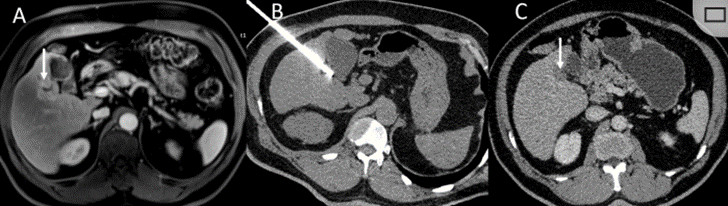

胆囊附近转移灶(来自子宫颈癌)的冷冻消融术

(A)门静脉期 CT 图像显示胆囊附近有病变(箭头)。

(B) PET-CT 图像显示病变处(箭头)。

(C) 手术过程中CT 显示冷冻探针位于病灶内。

(D)消融手术后 1 个月CT 显示完全消融。